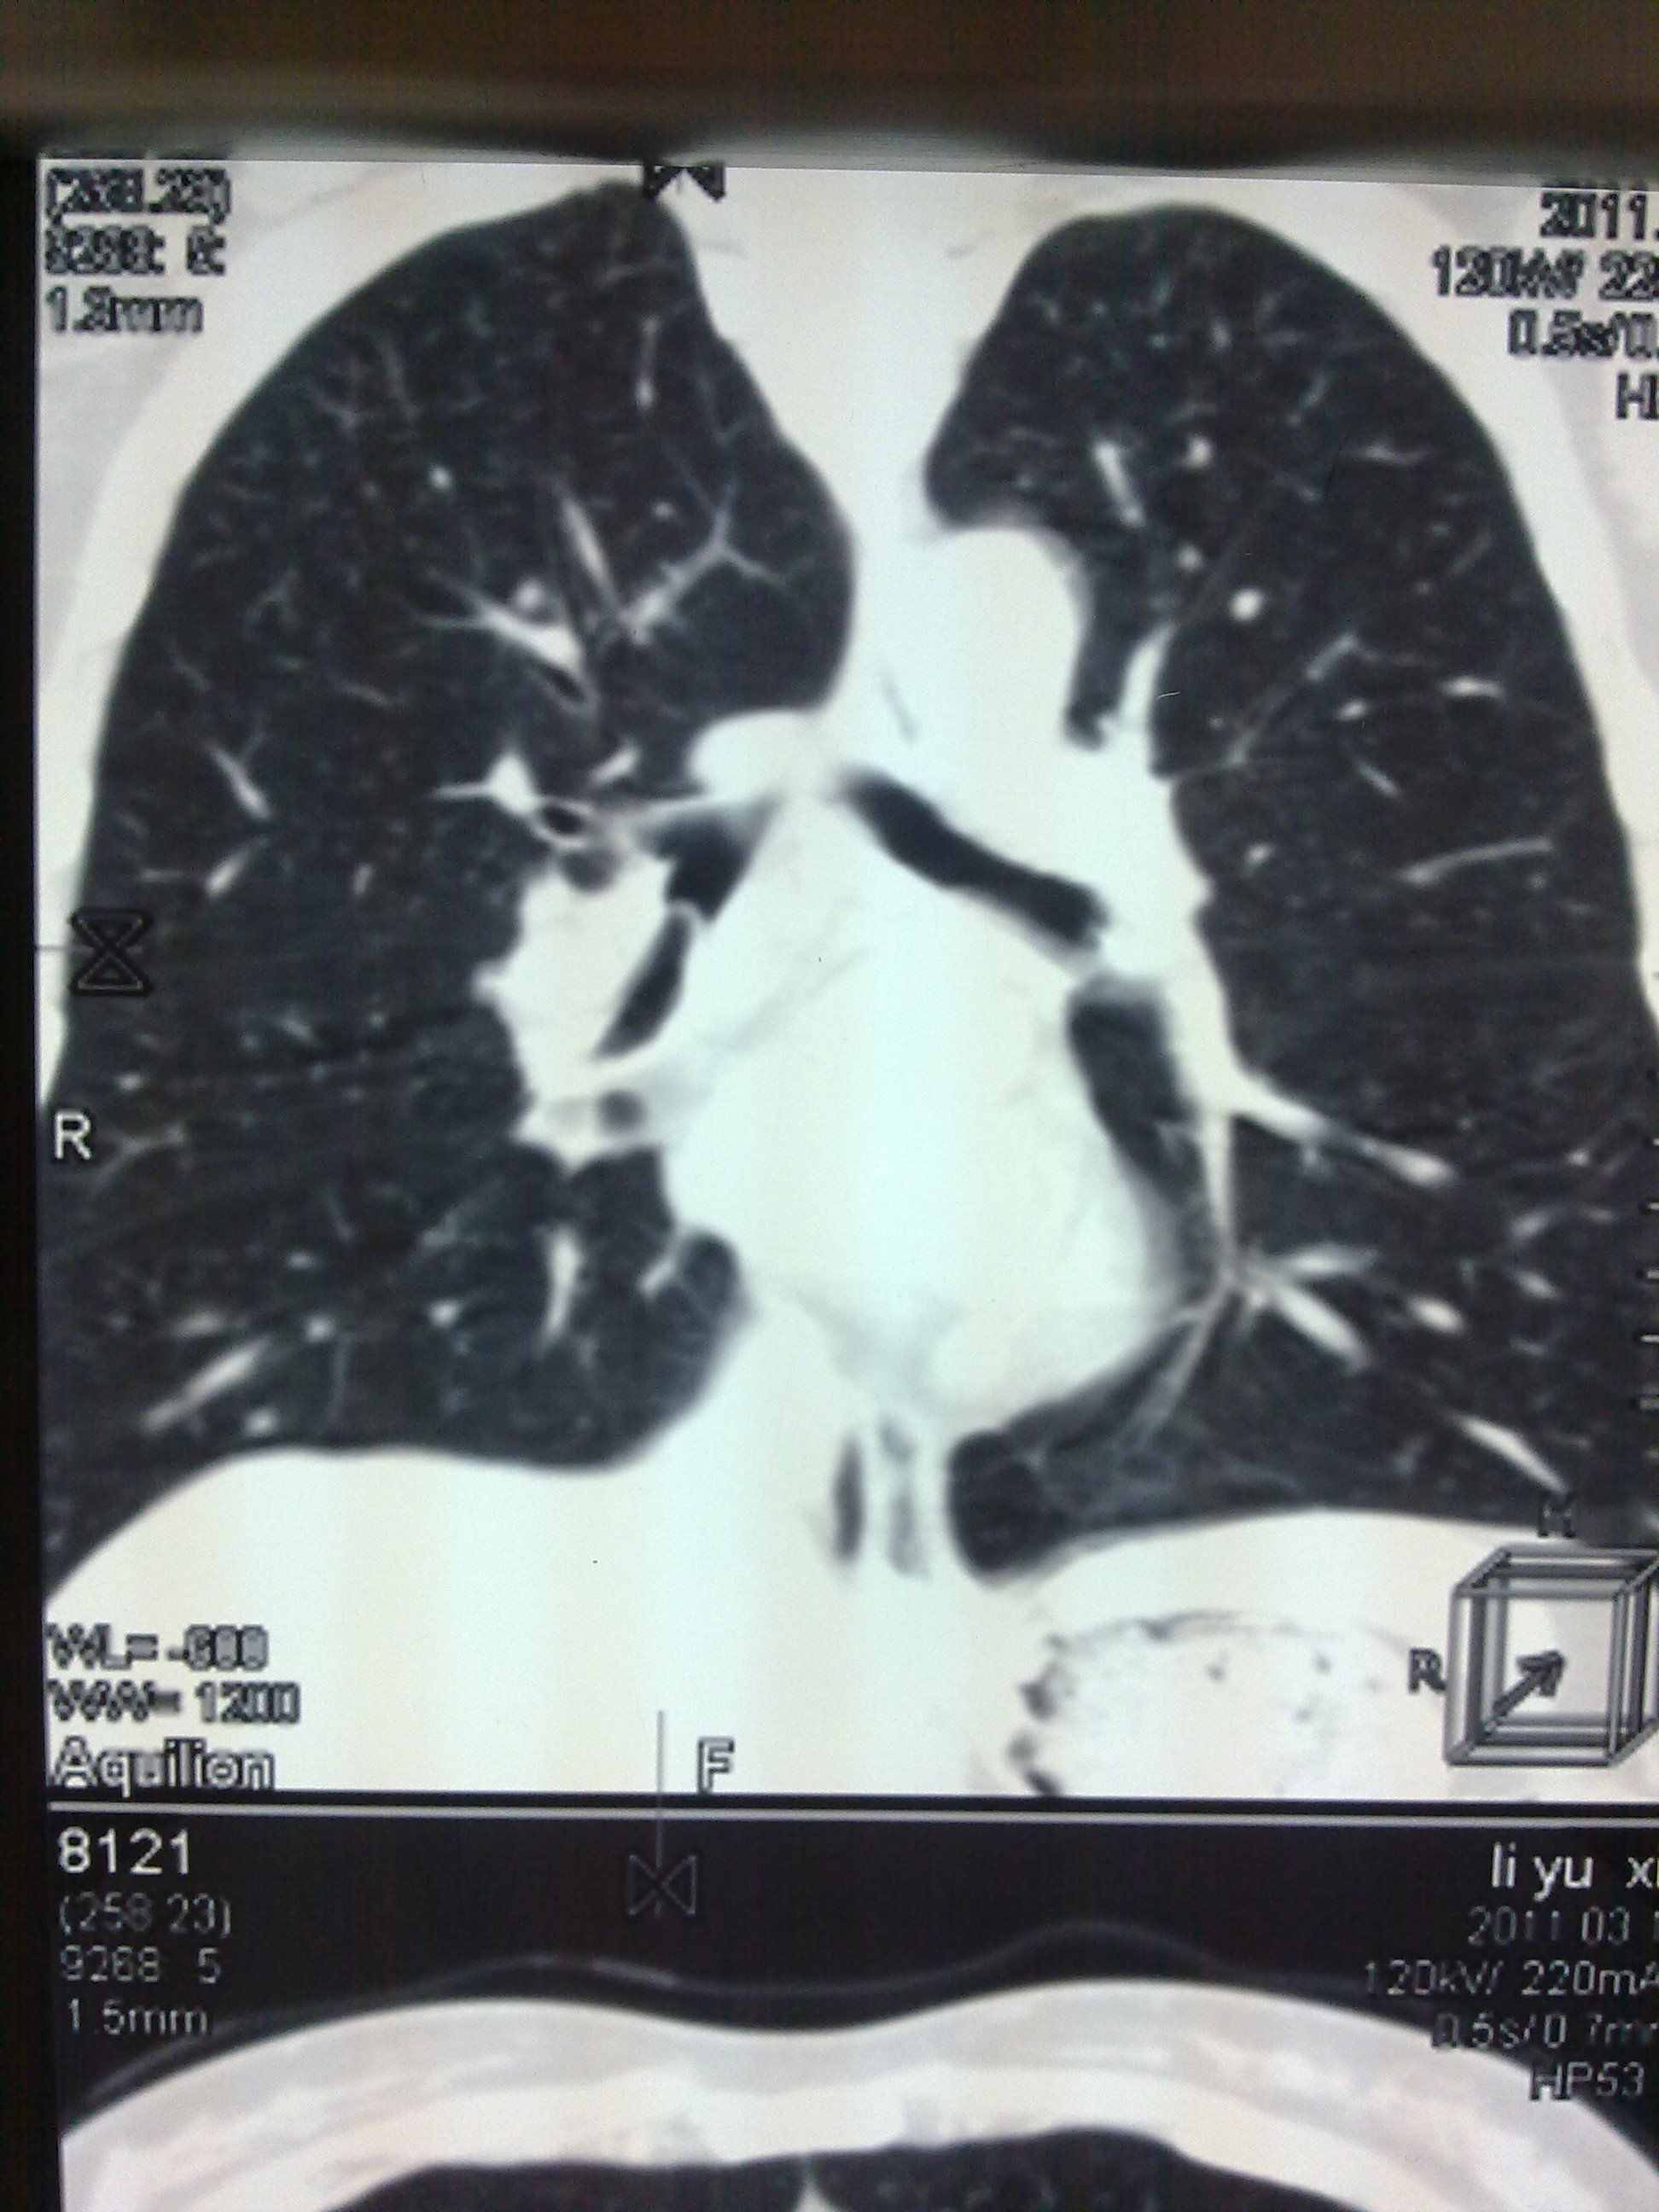

支气管异物ct图表现

支气管异物ct图表现,支气管异物

支气管异物的ct分析

支气管异物影像表现

支气管异物